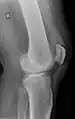

| An x-ray demonstrating quadriceps tendon rupture. Note the abnormal angle of the patella and soft-tissue swelling marked by the arrow. | |

A quadriceps tendon rupture is a tear of the tendon that runs from the quadriceps muscle to the top of the knee cap.[1]